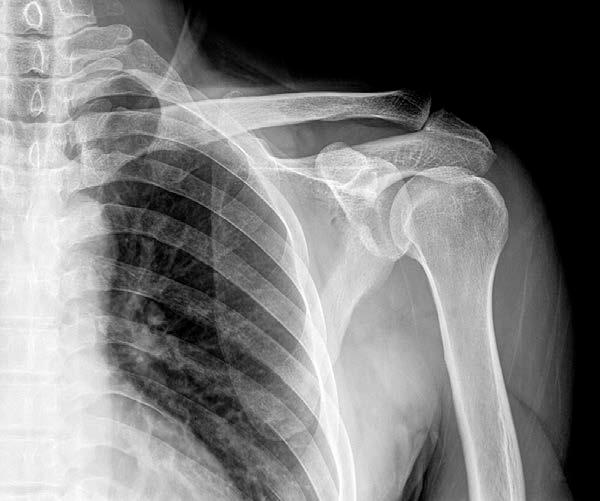

AudioLearn's Medical School Crash Courses presents Radiology

Written by experienced professors and professionally narrated for easy listening, this crash course is a valuable tool both during school and when preparing for the USMLE, or if you’re simply interested in the subject of Radiology.

The audio is focused and high-yield, covering the most important topics you might expect to learn in a typical Medical school Radiology course. Included are both capsule and detailed explanations of critical issues and topics you must know to master Radiology. The material is accurate, up to date and broken down into bite-sized sections. There are key takeaways following each chapter to drive home key points and quizzes to review commonly tested questions.